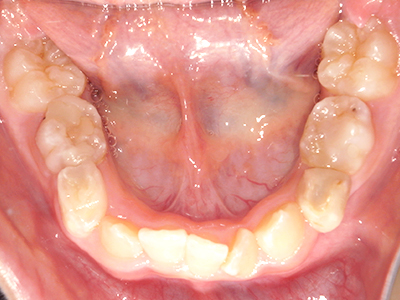

歯並びの相談に来られるお子様は、口呼吸をしているケースが多く、これが歯並びに大きな影響を与えています。

- 口呼吸をしている

↓ - 舌の位置が悪くなる

↓ - 頬の圧力が上の歯列にかかりやすくなる

↓ - 上あごが狭くなる

↓ - 下あごが狭くなる・下あごの位置が悪くなる

↓ - さまざまな不正咬合が生じる

ないき歯科クリニックでは、上あごの成長不足を補い、鼻呼吸を獲得しつつ歯列を整え、将来のお口をより健康な状態にすることをゴールに定める矯正治療をおこなっています。